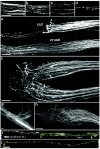

A direct histological assay of axonal regeneration would have many advantages over currently available behavioral, electrophysiological, and radiometric assays. We show that peripheral sensory axons marked with the yellow fluorescent protein in transgenic mice can be viewed transcutaneously in superficial nerves. Degenerating and regenerating axons can be followed in live animals with a dissecting microscope and then, after fixation, studied at high resolution by confocal microscopy. Using this approach, we document differences in regenerative ability after nerve transection, crush injury, and crush injury after a previous "conditioning" lesion. We also show that the chemotherapeutic drug vincristine rapidly but transiently blocks regeneration and that the immunosuppressive drug FK506 modestly enhances regeneration. Moreover, FK506 nearly restores normal regenerative ability in animals treated with submaximal doses of vincristine. Because neuropathy is the major dose-limiting side effect of vincristine, we propose that its efficacy could be enhanced by coadministration of FK506 analogs that are neuroactive but not immunosuppressive.